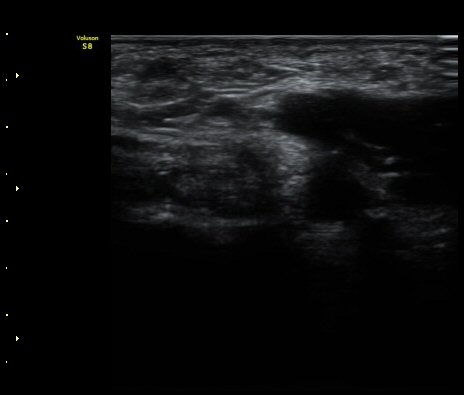

ÃÊÀ½ÆÄ °Ë»ç